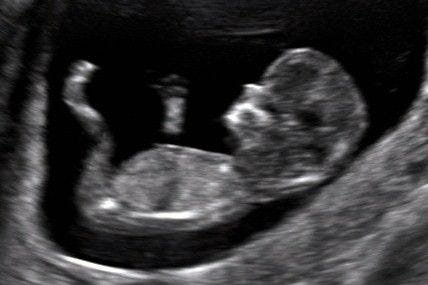

At Dr Shukl SDC Pathology Lab, we offer the Nuchal Translucency (NT) Scan as part of our comprehensive prenatal screening services. The NT scan is a non-invasive ultrasound examination performed around the 11th to 14th week of pregnancy to assess the risk of chromosomal abnormalities, particularly Down syndrome. This early screening provides valuable information that can guide further diagnostic testing and assist in making informed decisions about the pregnancy.

2. Nuchal Translucency Measurement: During the scan, the thickness of the fluid-filled space at the back of the baby’s neck (nuchal translucency) is measured. An increased measurement may indicate an elevated risk of chromosomal abnormalities.